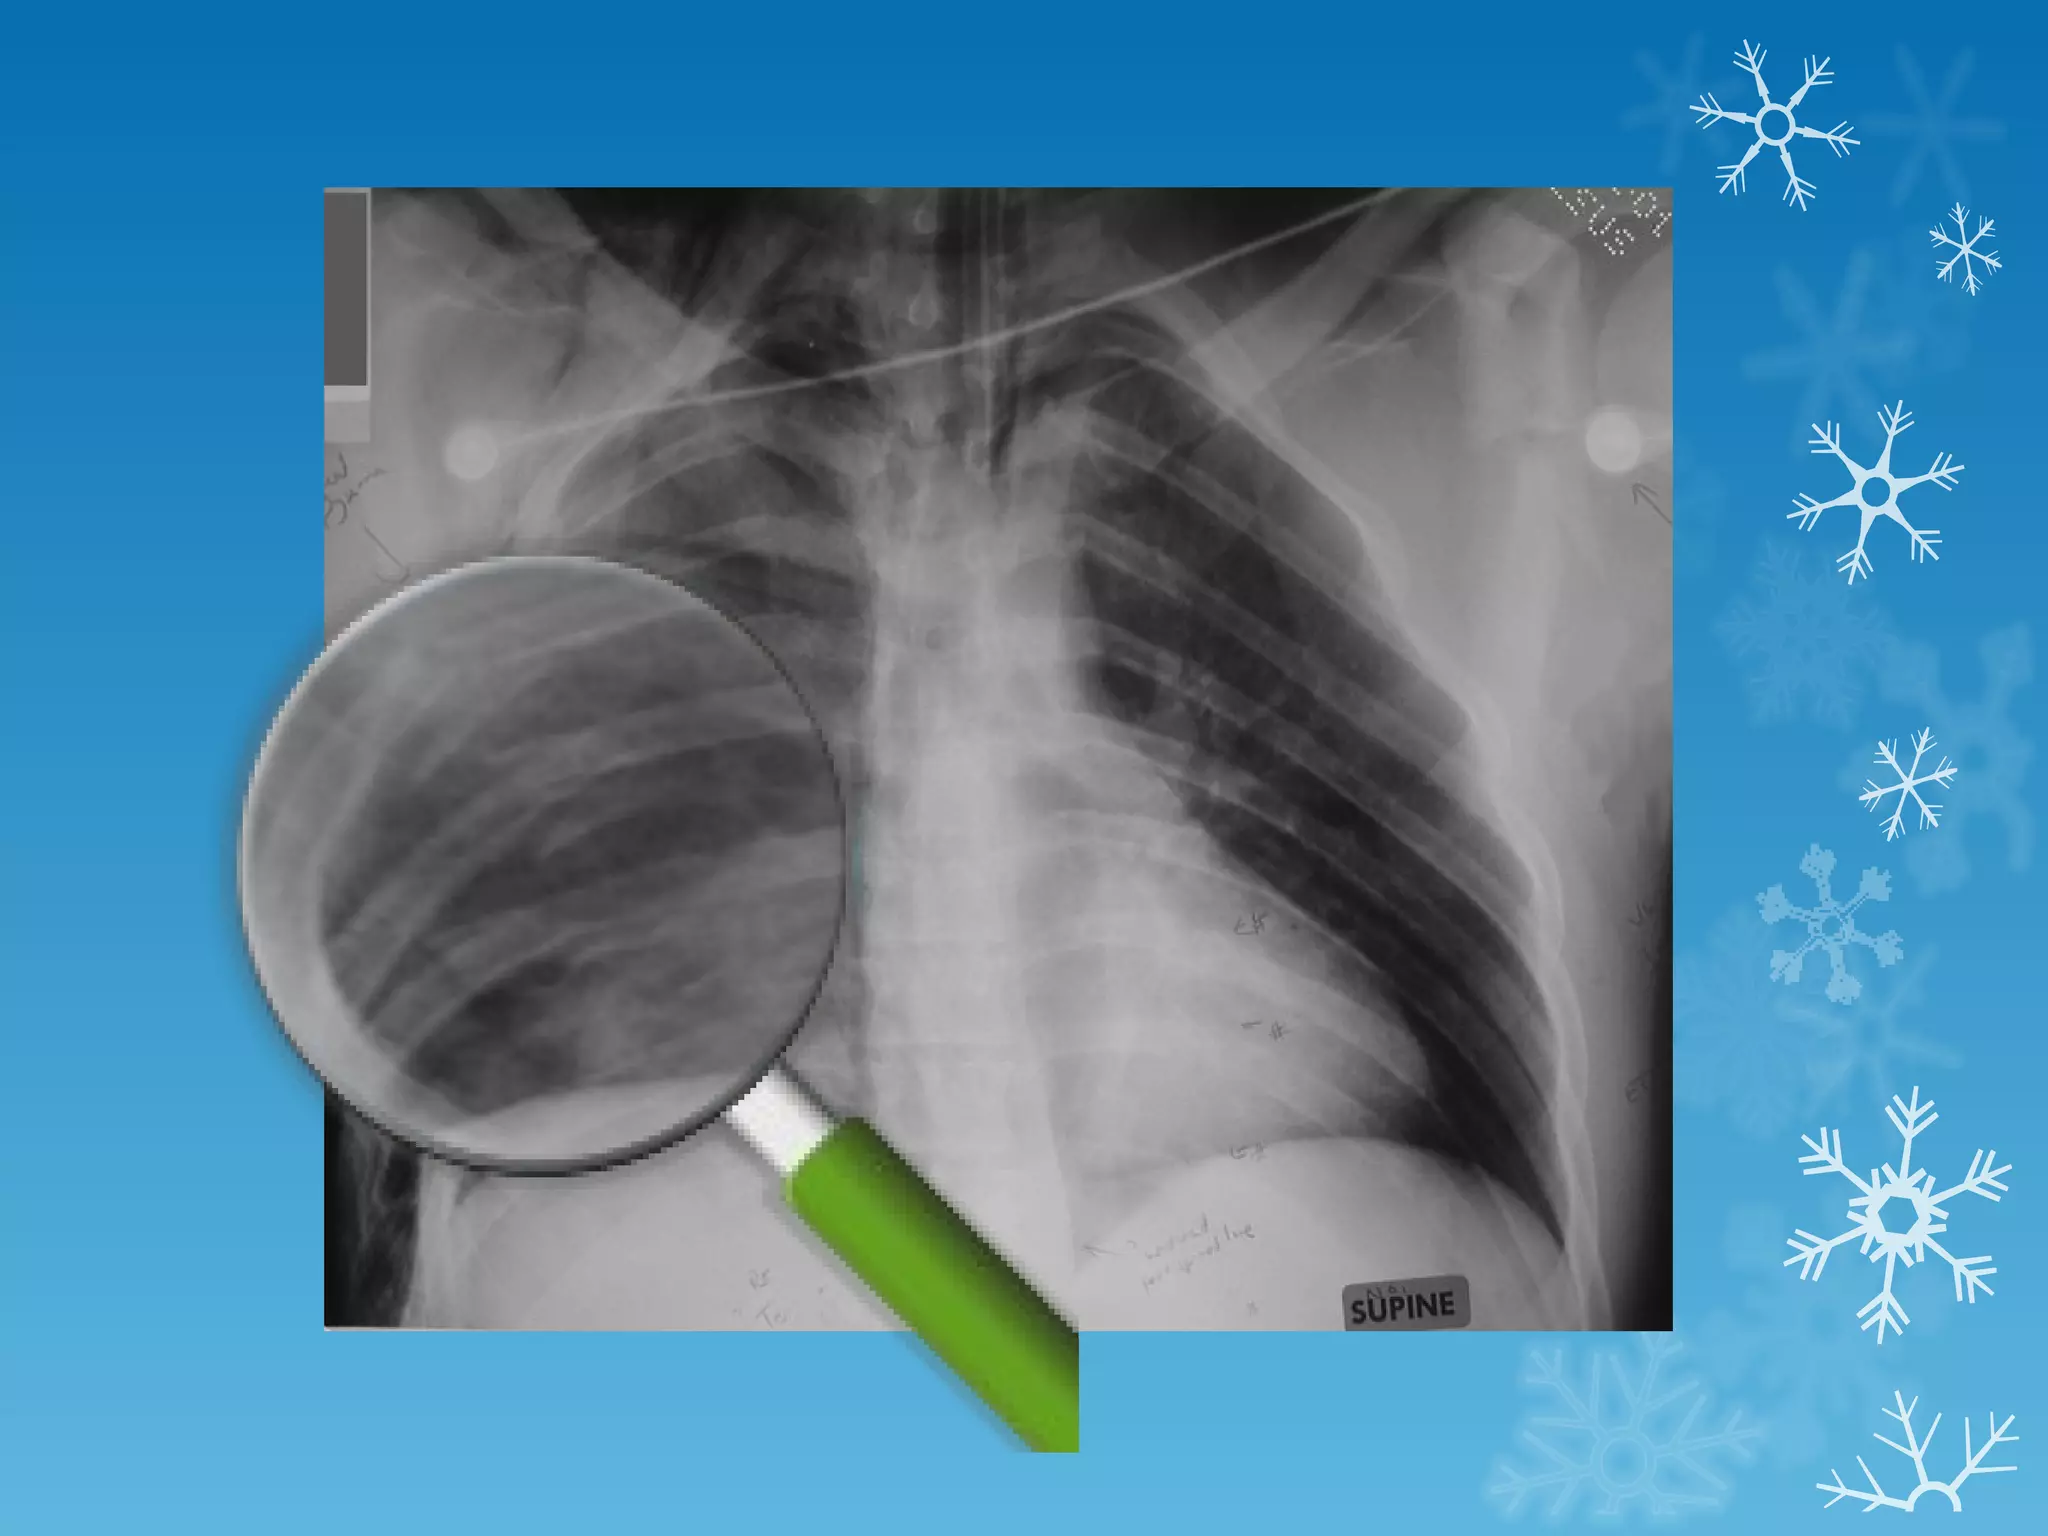

This document discusses chest x-ray interpretation and provides guidance on evaluating x-rays. It explains that tissue density determines how an x-ray beam penetrates, with denser tissues appearing whiter and less dense tissues appearing blacker. It also outlines different chest x-ray views and factors to consider like patient orientation, age, gender, and rotation. Abnormalities are described as appearing too white, too black, too large, or in the wrong place. The document stresses a systematic approach of identifying, localizing, describing lesions, and providing differential diagnoses.